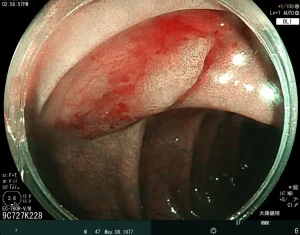

我們迎來豐田之山診所在手術房的第一台‘’黏膜下腫瘤切除術‘’。

這主要是切除大的胃腸道息肉或者黏膜下腫瘤。

葛振瑜醫師在高雄長庚醫院施行ESD的經驗豐厚。

當劉建宏醫師的找到第一個合適的患者,‘’一‘’就開始了。

在麻醉醫師的配合下,術式進行順利。世間又少了一個大腸癌的候選人。